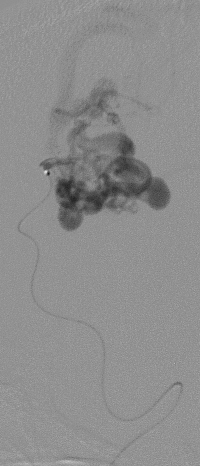

Durante el microcateterismo

La MAV fué erradicada de inmediato en forma definitiva como lo demuestra la angiorafía realizada 3 años después de la embolización con histoacryl + lipiodol (C).El paciente reanudó sus estudios habituales.